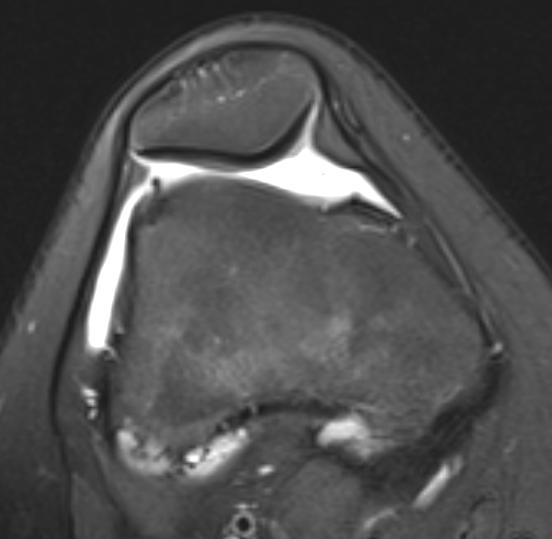

1. Recurrent subluxation + normal alignment (TTTG < 15 - 20)

- lateral release (only do if patella tilt / tight laterally or will dislocate medially)

- MPFL reconstruction / VMO advancement / medial reefing

2. Recurrent subluxation + malalignment (TTTG > 20)

- above + add TTT (tibial tuberosity transfer)